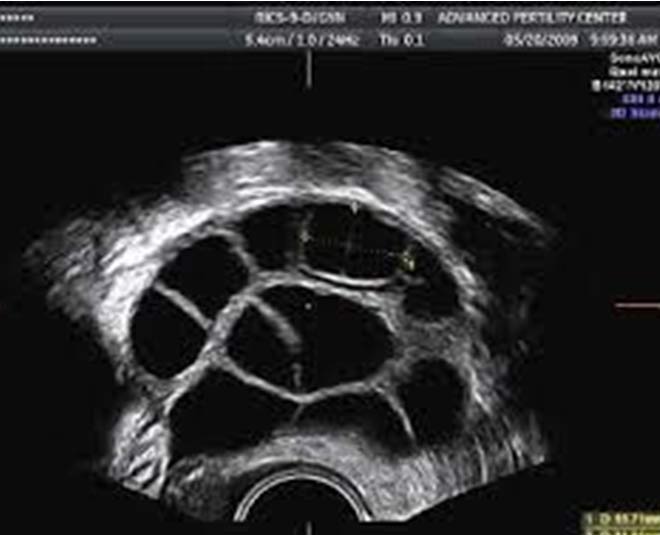

प्रोसेस के दौरान, आपका डॉक्टर अल्ट्रासाउंड के साथ ओवरी में फॉलिकल्स का पता लगाएंगे और एग्स को एक खोखली सुई से निकाल देंगे। प्रोसेस में आमतौर पर 30 मिनट से कम समय लगता है, लेकिन इसमें एक घंटे तक का समय लग सकता है।